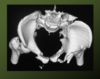

HN: The Pelvis, or Pelvic cavity is the region of the trunk inferoposterior to the Abdomen, between the Pelvic Brim and Pelvic Diaphragm. The Pelvis is also the transition point between trunk and Lower Extremity. The Perineum is the area of the trunk between the Thighs and Buttocks, from the Coccyx to the Pubis, inferior to the Pelvic Diaphragm.

The Bony Pelvis includes the Paired Coxal Bones, The Sacrum and the Coccyx. The Pelvic Girdle describes the paired Coxal Bone, which are joined anteriorly at the Pubic Symphysis.

The Bony Pelvis has a Superior and Inferior Pelvic Aperture. The Superior Pelvic Aperture (Pelvic Inlet) exists at the Pelvic Brim, between the Greater and Lesser Pelves, and is formed by the Sacral Promentory, Superior edge of the Sacral Ala, Arcuate Line of the Ilium, Pectin Pubis, posterior edge of the Pubic crest and superior edge of the Pubic Symphysis. The Inferior Pelvic Aperture (Pelvic Outlet) is bound by the inferior edge of the Pubic Symphysis, Inferior Pubic and Ischial Rami, Ischial Tuberosities, Sacrotuberous Ls. and the Coccyx. The Pelvic Canal is the passage between the two Apertures.

Sexual Differences in Pelves: Males have thicker, heavier Pelves, a deeper greater Pelvis, narrower and deeper lesser Pelvis, Android Pelvic Inlet, small Pelvic Outlet, narrow Pubic Arch, round Obturator Foramen and large Acetabulum. Females have thinner, lighter Pelves, a shallow greater Pelvis, wide and shallow lesser Pelvis, Gynecoid Pelvic Inlet, large Pelvic Outlet, wide Pubic Arch, oval-shaped Obturator Foramen and small Acetabulum.

Pelvic Fractures or crush fractures almost always involve multiple fractures given that the articulated Pelvis is a bony ring and therefore difficult to break in only one place. The Superior and Inferior Pubic Rami are often broken on both side as a result of this kind of injury.